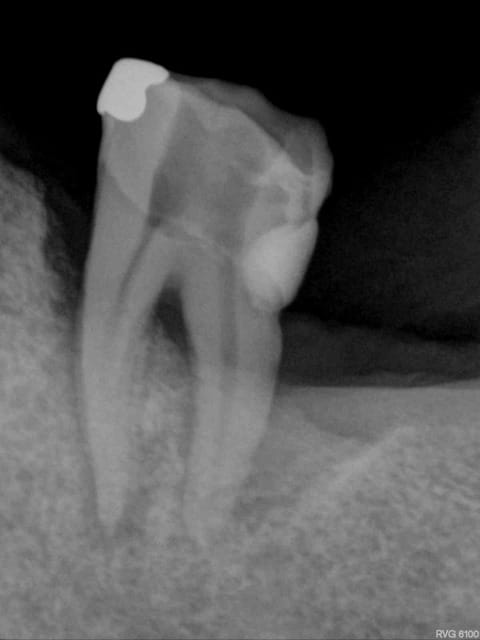

R 52 = 07/02/2011

R52 kzrddz - Eugenol